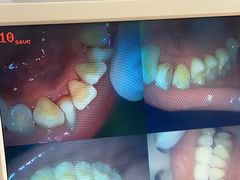

• 赫尔森口腔·牙齿种植修复

• -赫尔森口腔·牙齿种植修复

匿名用户 | 24-07-22